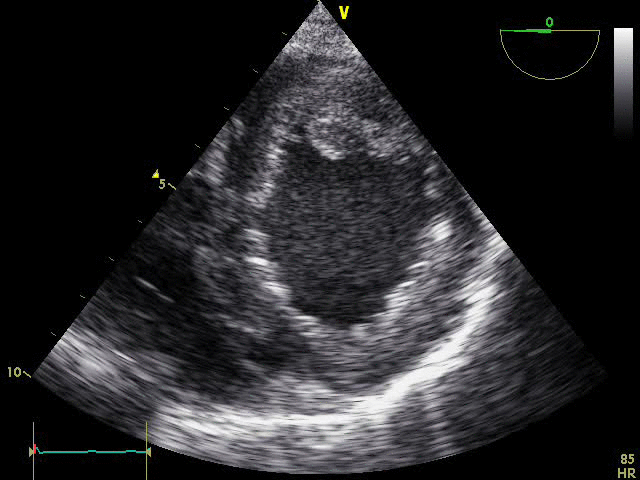

PSAX

EEU case image missing

PSAX View with Reduced Left Ventricular Function: Ultrasound clip showing a single PSAX view with reduced left ventricular function. Contraction is limited to the muscle in the upper and right part of the image, roughly from 12 o’clock to 6 o’clock, while the remaining myocardium shows little to no contraction, indicating impaired function.